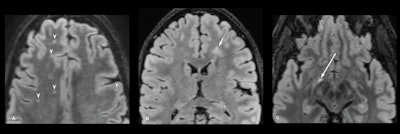

Axial FLAIR images of brain from baseline 3-T MRI examinations in 3 different participants with acute mTBI, showing abnormal WMHs based on varying criteria. (A) 41-year-old participant. Image shows five punctate hyperintense foci in frontal lobes (arrowheads), including four foci on the and one focus on left. (B) 16-year-old participant. Image shows 1-cm patchy hyperintense focus (arrow) in left frontal periventricular white matter. (C) 47-year-old participant. Image shows hyperintense focus in atypical location along right optic radiation (arrow). Images and caption courtesy of the ARRS.Axial FLAIR images of brain from baseline 3-T MRI examinations in 3 different participants with acute mTBI, showing abnormal WMHs based on varying criteria. (A) 41-year-old participant. Image shows five punctate hyperintense foci in frontal lobes (arrowheads), including four foci on the and one focus on left. (B) 16-year-old participant. Image shows 1-cm patchy hyperintense focus (arrow) in left frontal periventricular white matter. (C) 47-year-old participant. Image shows hyperintense focus in atypical location along right optic radiation (arrow). Images and caption courtesy of the ARRS.